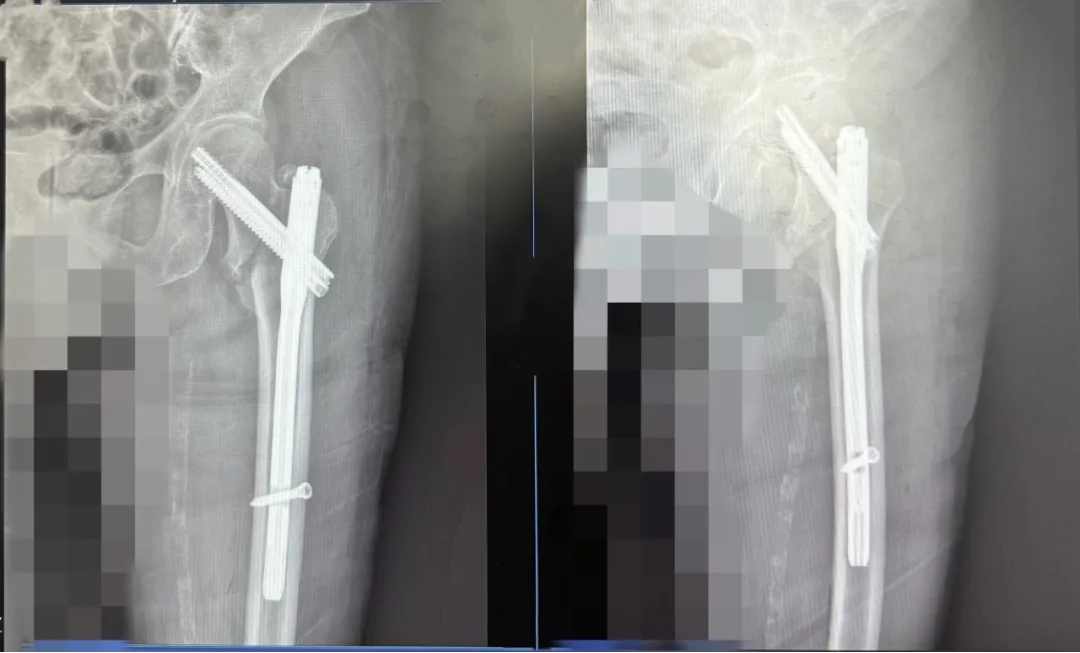

入院后,经完善相关检查,发现老人断端移位严重,有高血压、糖尿病、心肺功能差、重度骨质疏松等多种基础疾病,韦仁杰组织创伤手外科医疗团队对老人病情进行分析和讨论,最终决定采用微创闭合复位InTerTAN内固定术对老人进行治疗。术前一天,为缓解老人紧张、焦虑和恐惧的心理,韦仁杰专门带领创伤手外科医护团队到老人病房详细向患者及其家属告知了此次手术方案的治疗全过程及既往成功案例,缓解老人及其家属的焦虑情绪,并在此过程中认真倾听家属的疑问,耐心解答,让老人及其家属心里感到非常踏实。

经充分术前准备,在手术麻醉科的通力协作下,韦仁杰为老人实施了“微创闭合复位InTerTAN内固定术”,手术顺利完成。